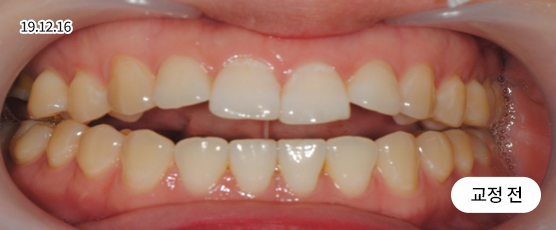

벌어진 치아교정 Solution

치아 벌어짐이 전체적으로 있는지 또는 부분(앞니 등)에만 있는지를 진단하고,

교정 장치를 부착하고 빈 공간으로 치아를 이동시켜 맞춰주는 방법으로 치료합니다.